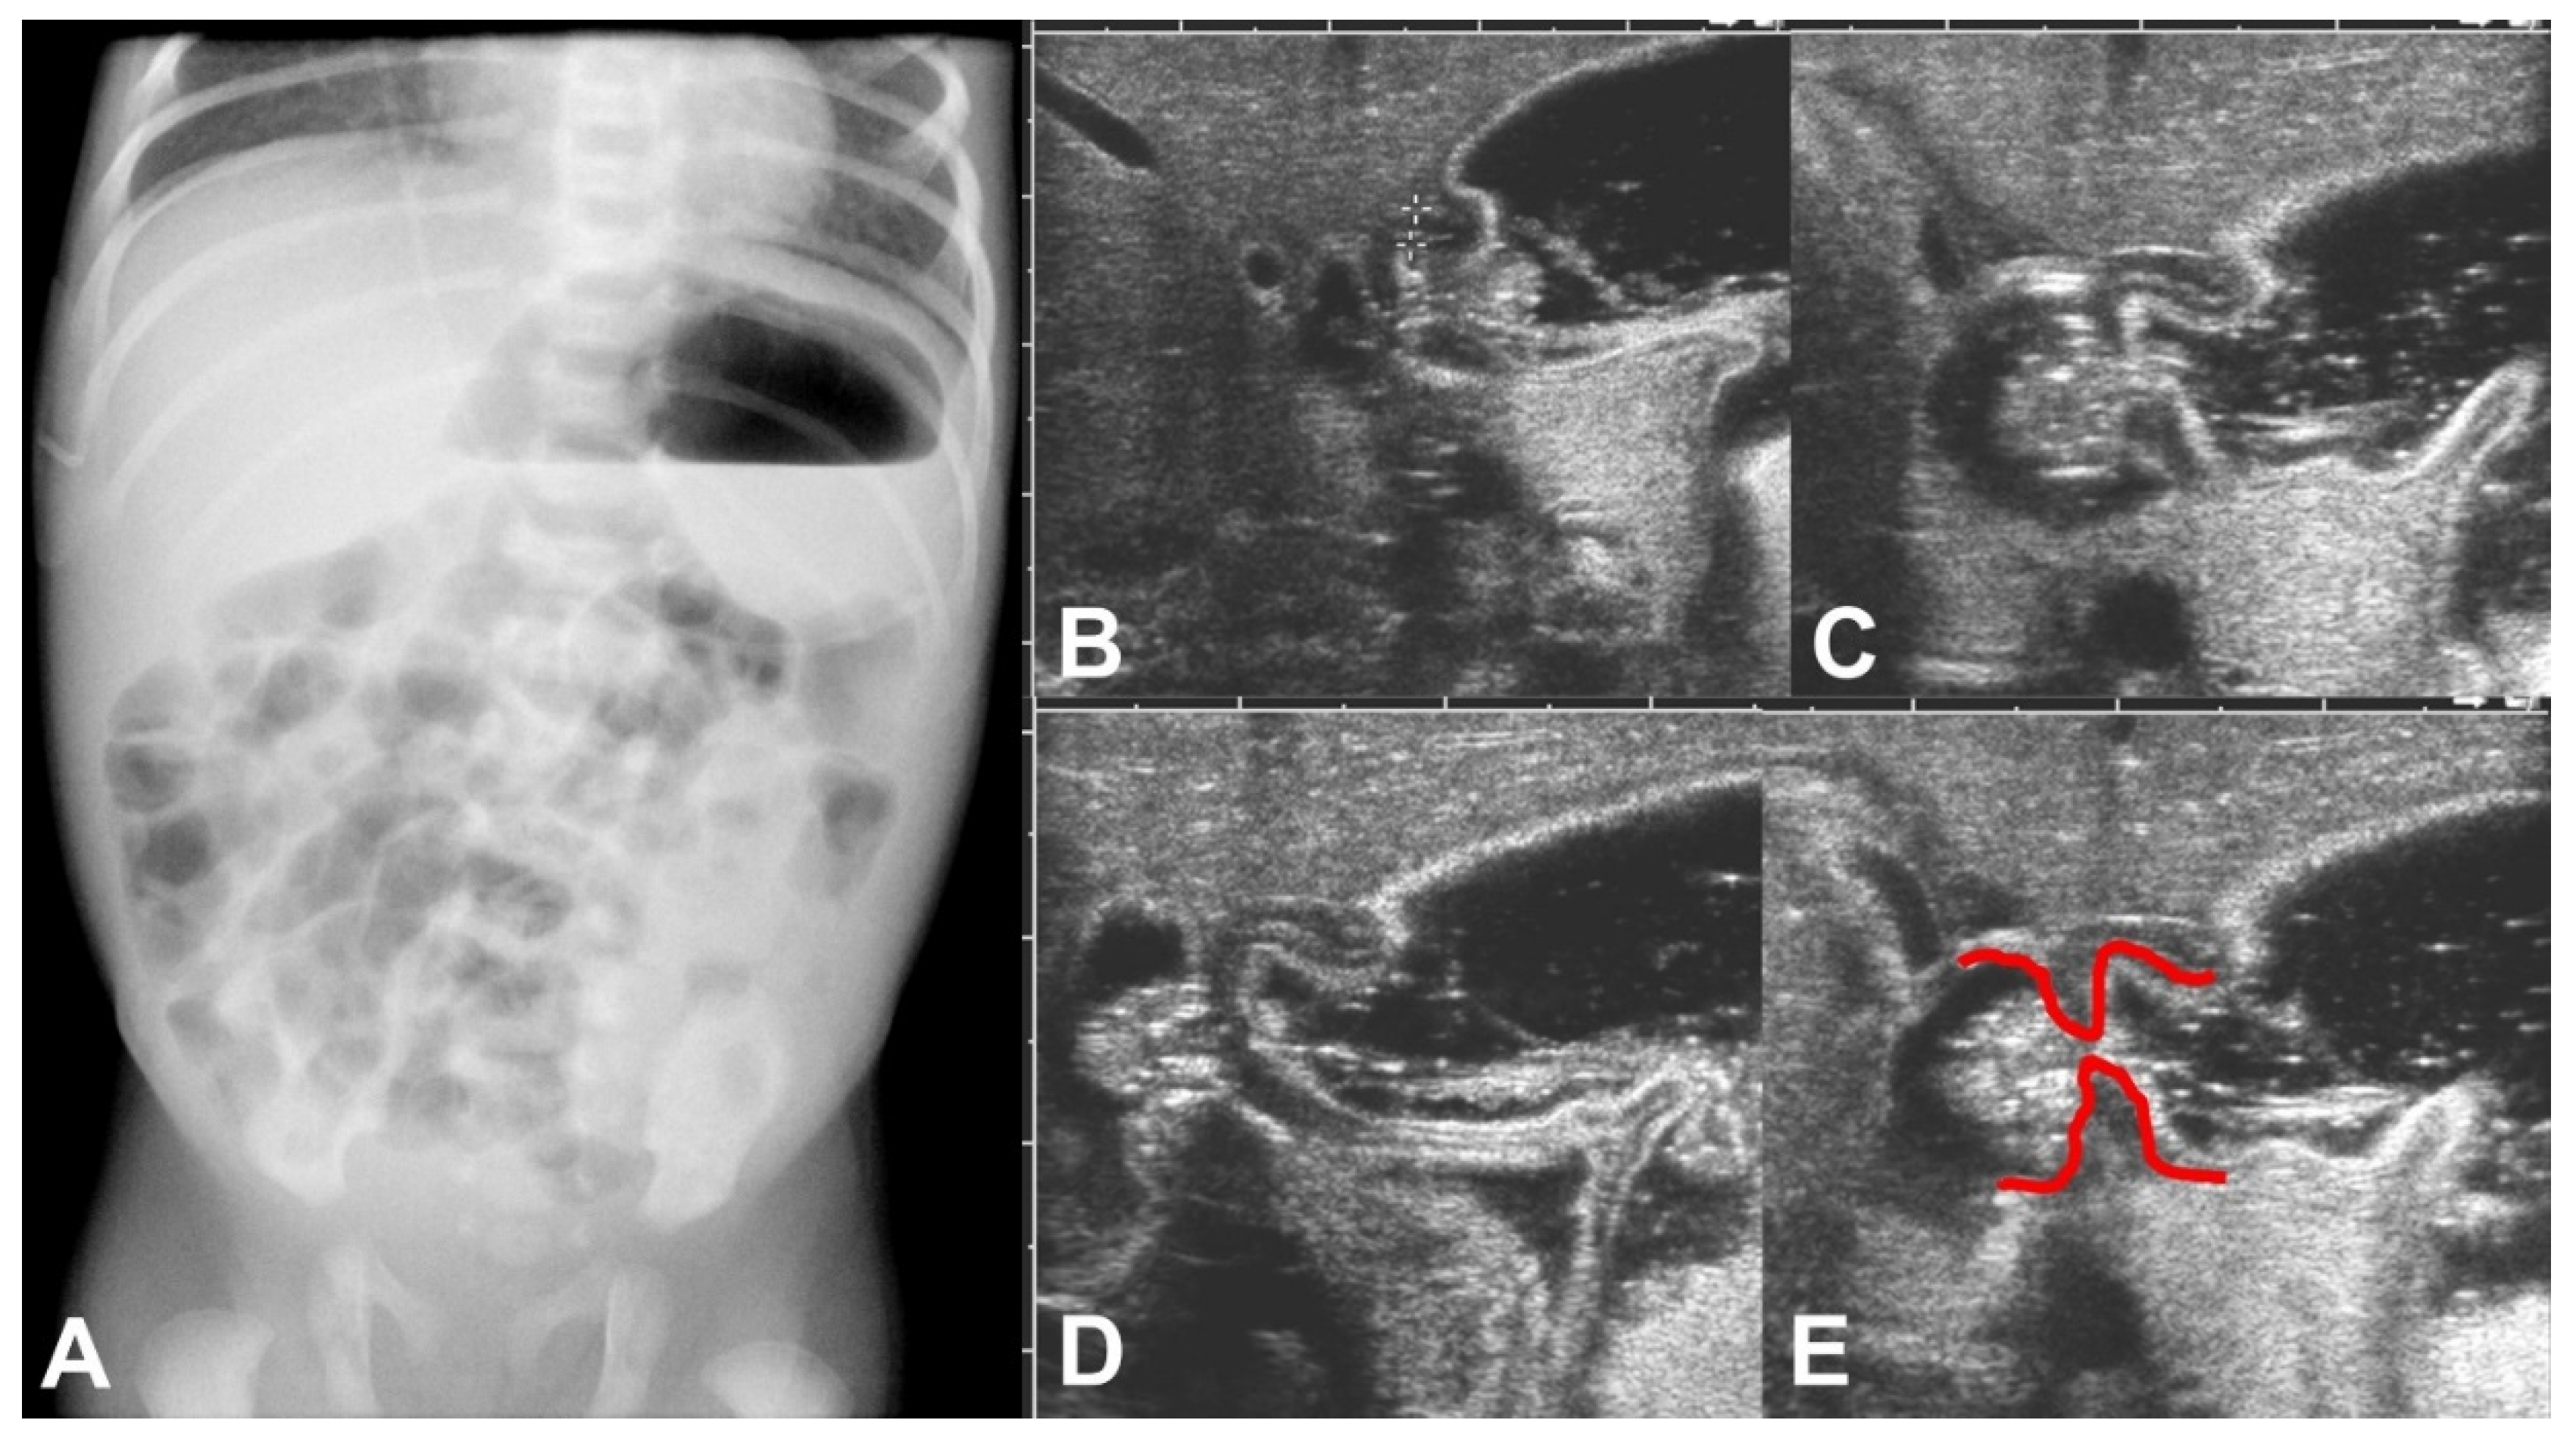

On the fifth day of life, a plain abdominal X-ray showed an enlarged stomach with an air-fluid level and an unsuspicious air distribution in the small bowel loops (Figure 1A). Ultrasound examination performed on the same day confirmed the finding of the enlarged stomach and added the information of functional gastric outlet obstruction because at no time during the examination an opening of the pylorus could be seen (Figure 1B–E). The thickness of the pyloric muscle was 3 mm, and the length of the pylorus was 1.3 cm.

Figure 1.

(A–E): (A) Erect plain abdominal X-ray on day 5 of life showed an enlarged stomach with an air-fluid level but was otherwise unsuspicious. (B–E) Sonographic examination on the same day showed a failure to pass gastric content, illustrated here in a sequence of ultrasound images during the gastric peristaltic wave. Furthermore, shouldering of the pylorus can be seen pointed out by red markings in (E).